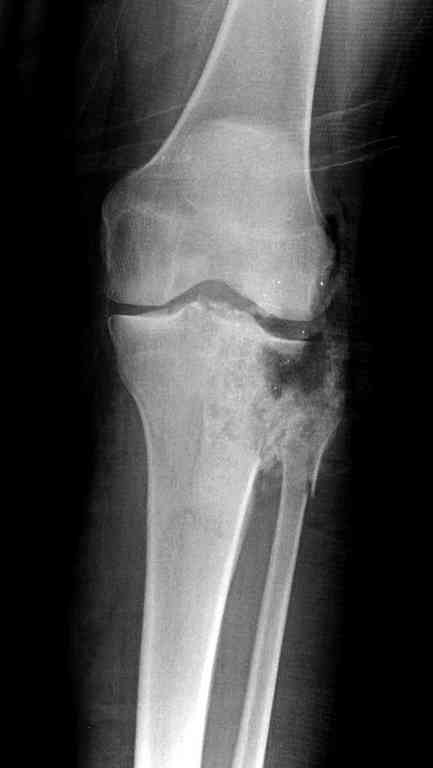

Поступила к нам пациентка 19 лет с диагнозом "Состояние после открытого многооскольчатого перелома дистального метаэпифиза правого бедра, проксимального метаэпифиза большеберцовой кости". Травма в июне 2010 года в Индии. ДТП.

Тамошние доктора выполнили ПХО с удалением фрагментов латерального мыщелка бедра. Наложен АВФ. По возвращению в Украину через 1,5 месяца АВФ демонтирован. И так как смещение фрагментов бедра не устранено, было принято решение после заживление ран от стержней выполнить МОС. Не сколько для четкой анатомической репозиции сколько для подготовки к установке эндопротеза в будущем. Что и было выполнено 10 августа. Интраоперационная картина следующая. Дефицит практически всего латерального мыщелка бедра. Была выполнена попытка закрепить то что осталось от мыщелка, но он развалился на фрагменты. ВЫполнен ситуационный синтез спицами. Дефект заполнили бикортикальным трансплантатом из крыла подвздошной кости, МОС страйкеровским фиксатором. В послеоперационном периоде к 10 дню начались боли, гипертермия. Повышение СОЭ, лейкоцитоз. Посев крови транзиторная бактериемия золотистого стаф. Взяли в операционную. Выполнили дренирование сустава и области п\о раны. Получили гематому фактически с гноем. Температура нормализовалась. Назначили ванкомицин по 1000 мг 2 раза в день.который принимает с 28 августа по сей день. Температура нормальная, СОЭ на убыль. Посевы отделяемого стафилококк 2 ст активности. Но отделяемое по дренажам продолжает идти в достаточном количестве. Взял посев, сеется стаф. 3 ст активноси. К ванкомицину, понятно, слабочувствителен. Что в этой ситуации посоветуете?

Все ипсилатеральные переломы относятся к категории нестабильных, и лечение их бывает сложным из-за двойного перелома вокруг сустава (floating joint). Основная тактика состоит в проведении поэтапного лечения с окончательной фиксацией cуставной поверхности.

На первом этапе с задачей справляется наружный фиксатор, который создает благоприятные условия для закрытия ран и контролирует длину конечности. На данном этапе рекомендована КТ, чтобы увидеть топографию фрагментов для расчета направления фиксирующих элементов.

Состояние мягкотканого покрытия подскажет о готовности к окончательной фиксации. При дефектах кости придерживаются тактики максимального сохранения костной массы.

Одинокий кортикальный шуруп не удержит тибиальный бугор, сустав тибиал плато оставлен без репозиции и фиксации.

План с протезированием чересчур агрессивный, больная слишком молодая. В данный момент для удержания конструкции необходимо установить наружный фиксатор между бедром и голенью. Обработку продолжать с применением антибиотиков и вакуумирования.